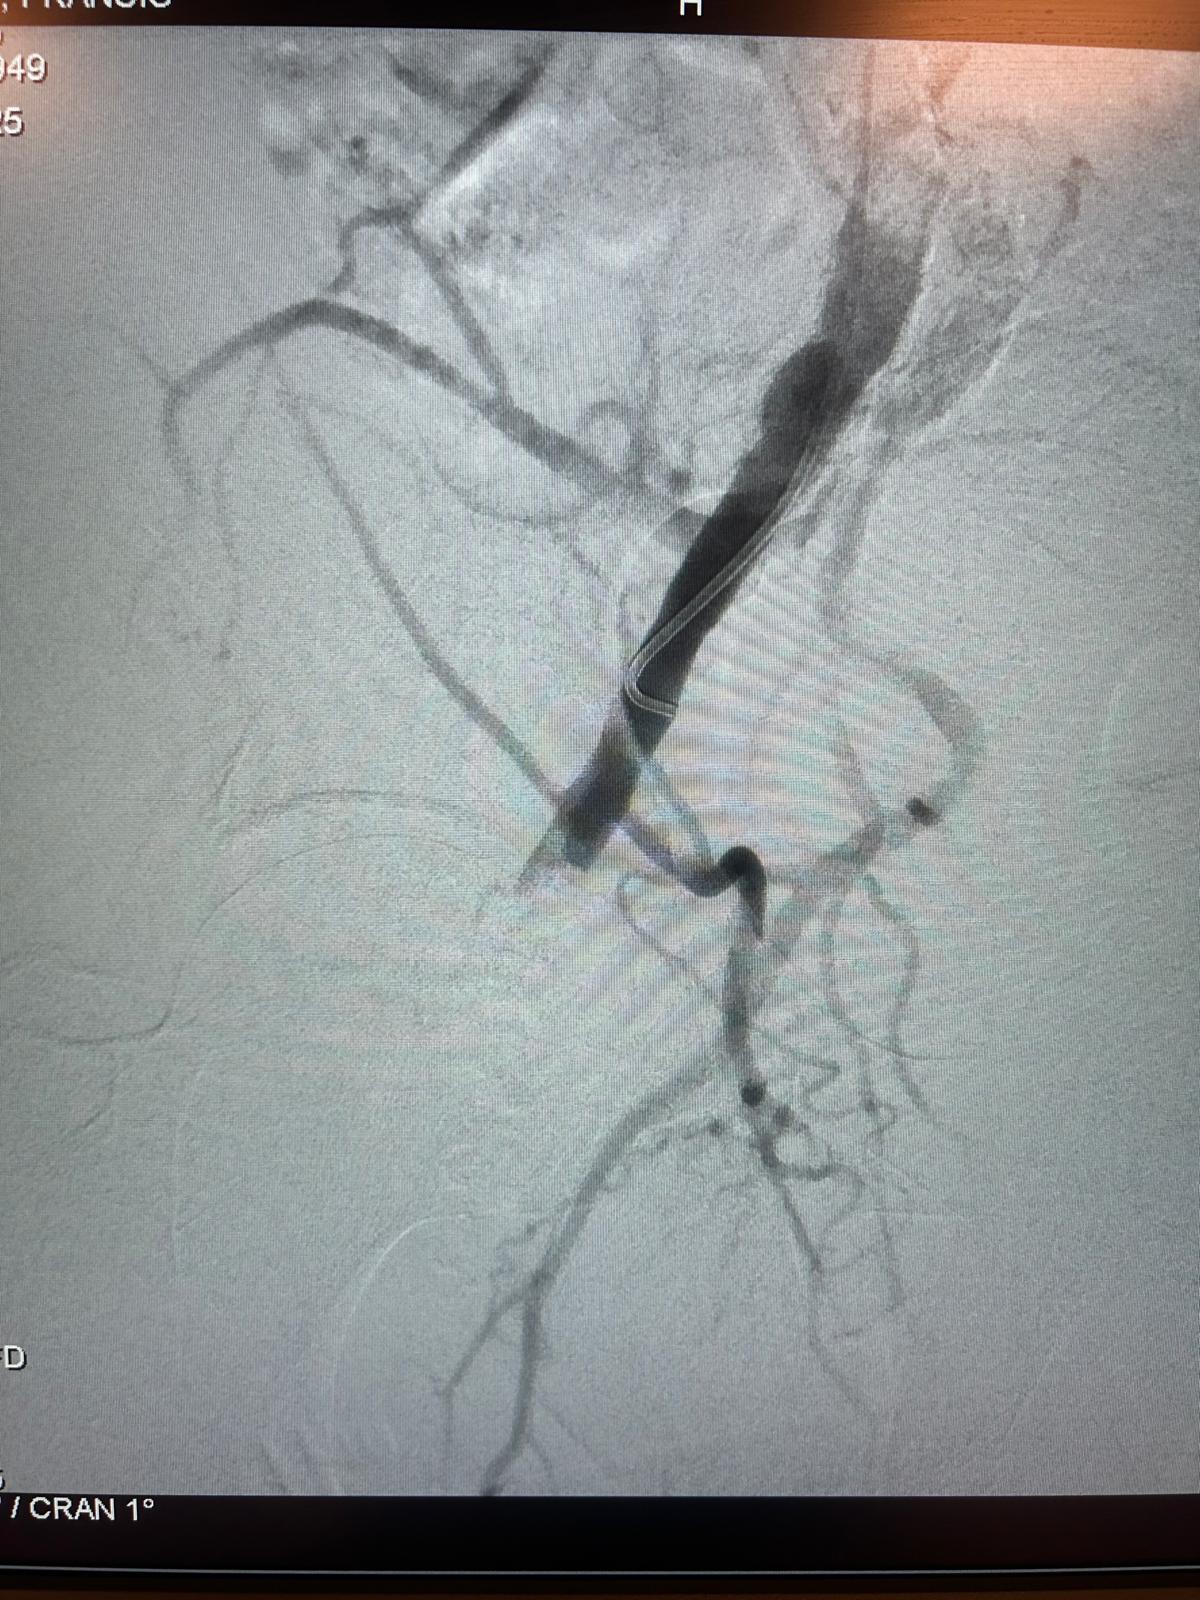

Patient âgé de 84 ans, présentant un Anévrisme de l'Aorte Abdominale sous-rénale, de plus de 55 mm de diamètre, douloureux, avec un collet aortique sous-rénal de 10 mm de hauteur, avec angulation antérieure de 20 degrés, sans thrombus circonférentiel, rapidement conique.

Antécédents de cardiopathie ischémique sévère et de stenting coronarien récent rendant le patient à haut risque chirurgical pour une mise à plat greffe aortique en urgence.

Le caractère douloureux de l'AAA ne permet pas d'attendre la conception et la mise en place d'une endoprothèse aortique fenestrée.

Fuite de type IA persistante au contrôle artériographique per-opératoire après inflation prolongée du collet aortique proximal et de la totalité de l'endoprothèse aortique à l'aide d'un ballon ENDURANT. Pas de possibilité de mettre en place une CUFF aortique plus proximale.

Mise en place de 8 Heli-FX EndoAnchor en "STOCK", mises en "croix", au niveau du collet aortique sous-rénal, juste en aval de l'artère rénale gauche.

Disparition immédiate et complète de la fuite de type IA sans nouvelle inflation du corps de l'endoprothèse.